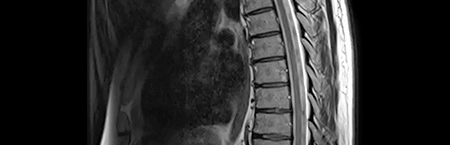

• Ressonância magnética do neuroeixo

Ressonância magnética

• Carga lesional extensa

• Inúmeras novas lesões em relação a RM prévia

• Ressonância magnética

• "aumento do número de lesões supratentoriais (…) no estudo medular não se destacam seguras lesões de novo"

• Ressonância magnética de rebaselining 6m após início de terapêutica

• Apresentava estabilidade da carga lesional supratentorial, e ausência de lesões captantes

• Referência a nova lesão em D6